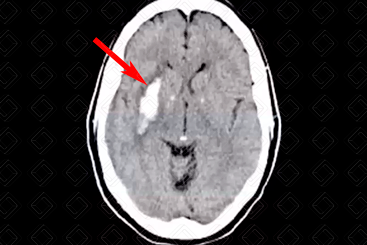

Texto alternativo para a imagem Figura 1. Créditos: Dra. Elazir Mota - Rio de Janeiro/RJ

Descrição da figura 1: Imagem espontaneamente densa no putâmen direito com halo de edema circunjacente (seta vermelha), compatível com sangramento, em paciente hipertenso.

• Hemorragia hipertensiva: Hematoma focal agudo ou micro-hemorragias. Localizações mais comuns: putâmen e cápsula externa (mais comuns, cerca de 60-65% dos casos). Outras localizações típicas são tálamo, centro semioval, cerebelo e ponte (f iguras 1 e 2);

• Tomografia computadorizada (TC) do crânio: Exame de escolha nos pacientes que estão na emergência e precisam de rápida definição a respeito da presença de sangramento ou não e sua extensão. Na maioria dos casos, nas fases agudas , o sangramento apresenta-se como imagem espontaneamente densa na TC em geral, superior a 50 UH (única exceção são nos pacientes com anemia extrema ou distúrbios da coagulação, quando os hematomas agudos podem se apresentar isodensos na imagem). Já na fase subaguda (por volta de 1-6 semanas), o hematoma costuma apresentar-se isodenso ao parênquima na tomografia. Na forma crônica , eles são hipodensos ;